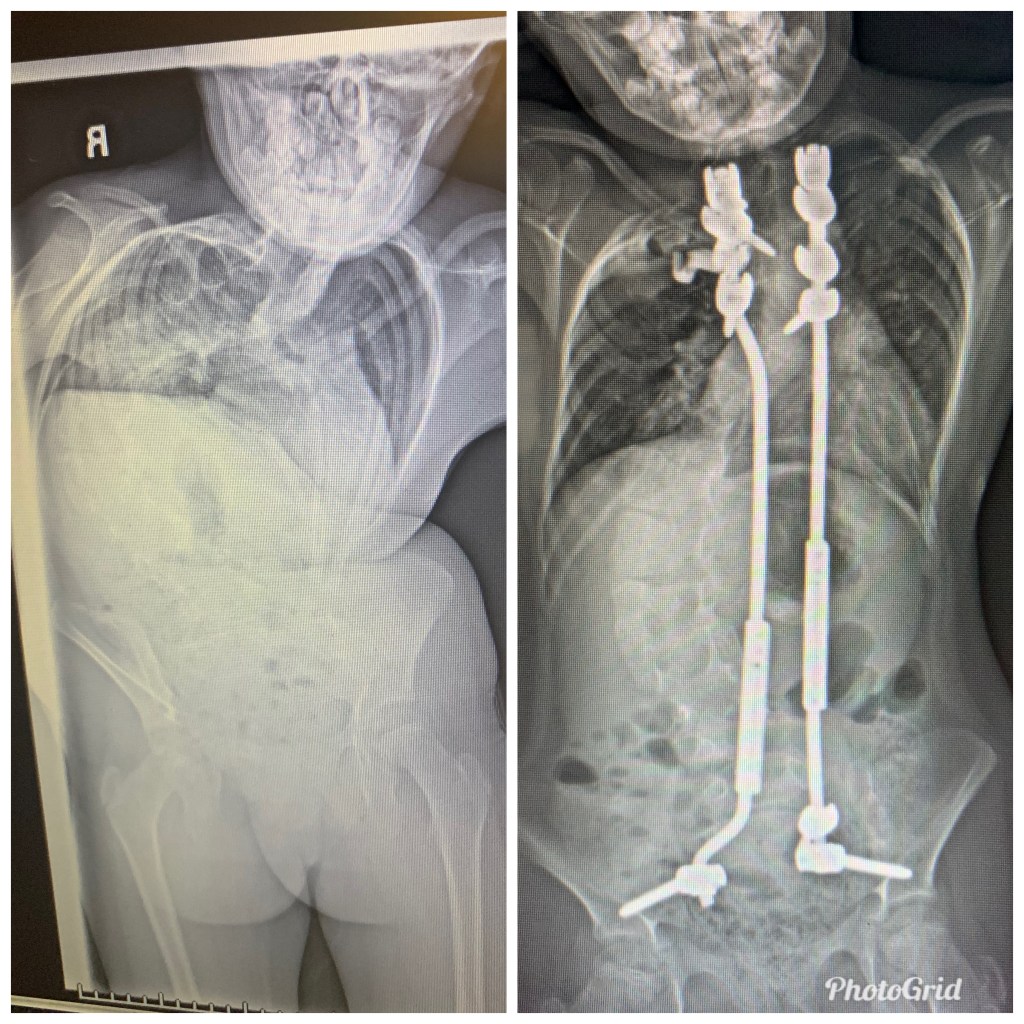

Post-Op Surgery #25: Halo removal & rod insertion A few days after Surgery #25Tenleigh after the halo application was removed!

Before & After Halo Gravity TractionHalo Gravity TractionPost-op Halo Application SurgerySurgery #25: Halo Removal & Rod Implantation at Boston Children’s HospitalHalo Gravity Traction (HGT)

Tenleigh Joy Stokes is the 14-year-old daughter of Lee Stokes and Haylee Shrake of Pana, Illinois. At thirty-two weeks’ gestation, Haylee unexpectedly started showing severe signs of pre-eclampsia, resulting into HELLP Syndrome (hemolysis, elevated liver enzymes, and low platelet counts). Weighing 2 pounds 6.6 ounces and 14.6 inches long, Tenleigh was induced into this world on March 23, 2012. Due to her prematurity, Tenleigh remained at St. John’s Hospital in Springfield, Illinois for thirty days in the Neonatal Intensive Care Unit (NICU). Aside from being small, she appeared to be your average healthy newborn. However, at four months old she shocked doctors in central IL with a never before seen condition. Tenleigh’s physician ordered an X-ray in concerns of a respiratory infection after noticing that she was “tugging” to breathe. The X-ray showed multiple skeletal abnormalities including scoliosis, torticollis, hemi-vertebrae’s, a small chest wall, along with fused and missing ribs. Doctors across Illinois were left speechless due the complexity of Tenleigh’s unknown condition. The doctors unanimously confirmed that without surgery, Tenleigh would not survive infancy. Eventually her spine would crush her lungs causing her own ribs to puncture her lung and suffocate. As the months passed, Tenleigh’s condition worsened. She was admitted repeatedly for respiratory infections, including two weeks in the Pediatric Intensive Care Unit (PICU) for respiratory syncytial virus (RSV). Despite the poor prognosis, Tenleigh’s parents did not give up hope. After taking research into their own hands, the twenty and twenty-one-year-old parents found hope thirteen hours away from home at the Children’s Hospital of Philadelphia (CHOP). Dr. Robert Campbell Jr., known for inventing the life saving device called the Vertical Expandable Prosthetic Titanium Rib (VEPTR). The device was created to treat children with rare syndromes and disorders that involved malformed rib cages or missing ribs. The first implantation took place in 1989 but has been modified since to accommodate more critically ill children: “On Aug. 23, 2004, the U.S. Food and Drug Administration approved VEPTR (H030009) as a medical device under the Humanitarian Device Exemption Program. A Humanitarian Use Device is intended to treat or diagnose a disease or condition — such as thoracic insufficiency syndrome — that affects fewer than 4,000 people in the U.S. per year” (www.chop.edu). In May 2013, Tenleigh, her parents, and grandparents drove out to Philadelphia, PA for a consultation with Dr. Campbell. During the consultation, the family was finally given a name for Tenleigh’s unknown condition, spondylocostal dysplasia. According to the National Organization for Rare Diseases, the exact prevalence of spondylocostal dysplasia is unknown. In severe cases like Tenleigh, deformities of the chest, spine and ribs prevent normal breathing, lung growth and lung development. The inability to expand the chest sufficiently causes a decrease in lung capacity, known as Thoracic Insufficiency Syndrome. These malformations increase the risk for repeated respiratory infections, difficulty breathing, pulmonary hypertension, heart failure, chronic back pain, etc. Due to the complexity and severity of Tenleigh’s disorder, Dr. Campbell recommended coming back in August to run tests and ultimately implant the VEPTRs. Tenleigh was admitted to the Children’s Hospital of Philadelphia eight days prior to surgery for monitoring and testing. On August 20, 2013, Tenleigh had her fused ribs separated and two VEPTR rods implanted on both sides of her spine. The top of the VEPTR was clipped around an upper rib and anchored to her pelvis. The surgery was a success and twenty-four hours later, Tenleigh came off the ventilator. She remained hospitalized for a week, before beginning her six-week recovery at home. For the first year and a half, Tenleigh battled repeated staphylococcus aureus infections. Tenleigh was transferred twice via jet from St. John’s Children’s Hospital to the Children’s Hospital of Philadelphia. The repeated infections resulted in a Peripherally Inserted Central Catheter (PICC Line) for antibiotics, negative pressure wound therapy (NPWT or Wound VAC) to clean her open wound, multiple debridement surgeries, removal of her left VEPTR rod and placement of a gastronomy tube. After nine surgeries within a year and a half, Tenleigh finally caught a break. Although Tenleigh remained healthy, the family had more unexpected battles. Since birth, Tenleigh has relied on Medicaid to fund the majority of her expenses. The family was initially informed that if they were to pay in full, the VEPTR implantation would be approximately $100,000. Each VEPTR expansion performed every four to six months would be approximately $20,000 and a VEPTR revision or exchange would be in the middle. In the Spring of 2015, CHOP informed the parents that Illinois Medicaid had not paid any of the bills and was refusing to fund future surgeries. The family hit a breakthrough after many letters from Dr. Campbell, Illinois doctors, Illinois State Representatives, along with the power of the news and social media. When the family arrived for Tenleigh’s VEPTR expansion, they were informed that Dr. Campbell had an unexpected death and would have to reschedule. Tenleigh had gone almost seven months without surgery due to insurance and was experiencing significant pain. Dr. Campbell suggested having his new partner, Dr. Cahill perform the surgery. The parents agreed and the surgery appeared to be a success. The following month after surgery, Tenleigh’s left VEPTR started to prominently appear. Although she was not complaining of pain, it looked as if the rod could come through her skin at any time. However, Dr. Campbell’s health became compromised and the family had to transfer care to Dr. Cahill in order to have immediate surgery. Tenleigh’s VEPTR had completely eroded through her ribs and needed to be reattached. Unfortunately, Tenleigh often needed revision surgeries in between her VEPTR expansions over the course of the next year and a half. On April 25, 2018, Tenleigh was scheduled for a VEPTR revision and expansion. However, due to an uninformed decision made by the medical personnel, MAGnetic Expansion Control (MAGEC) growing rods were implanted in place of Tenleigh’s VEPTR’s. Tenleigh spent twenty days hospitalized from complications related to the MAGEC rods. Tenleigh’s body rejected the rods, requiring two transfers from St. John’s Hospital to the Children’s Hospital of Philadelphia. The complications resulted in removing both MAGEC rods until Tenleigh could recover. Tenleigh spent over a year recovering from infections, skin breakdown, and trying to gain weight. She was also required to wear a Thoracic Lumbar Sacral Orthosis (TLSO) brace to prevent her spine from progressing. The plan was to postpone another implantation surgery until Tenleigh gained sufficient weight or if she began to experience respiratory complications. However, during the summer of 2019, Tenleigh started to become short of breath and severe back pain. A local x-ray showed that Tenleigh’s degree of spinal curvature had increased from 97 degrees to 120 degrees within three months. Due to the severity of Tenleigh’s condition progressing, a halo gravity traction was recommended by Dr. Emans at Boston Children’s Hospital. On January 01, 2020, the family began their undetermined extended stay at Boston Children’s Hospital. Tenleigh had the halo application applied to her skull with four pins on January 07, 2020, spending the next month attached to a weighted pulley system to naturally lengthen her spine. On February 06, 2020, Dr. Emans removed the halo and implanted two customized growing rods. The results were phenomenal! Tenleigh’s Cobb Angle (spinal degree of curvature) improved from approximately 120-130 degrees to 60-70 degrees! Tenleigh immediately felt relief and could preform her activities of daily living (ADL’s) better than before! She continued to impress the doctors and recovered at lightning speed! After 59 days away from home, the family finally returned home on February 28, 2020.